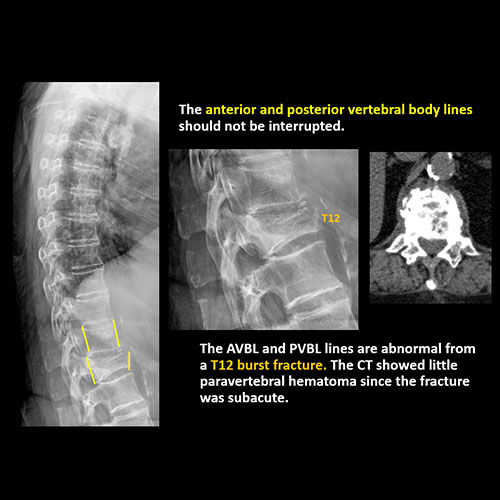

The anterior and posterior vertebral body lines are abnormal or interrupted. |

Yes | NA |

There is an oblique fracture with avulsion through the anterior inferior T9 vertebral body. The posterior elements are intact. There is excessive calcification of the anterior longitudinal ligament and there are continuous osteophytes in a pattern consistent with DISH (Diffuse Idiopathic Skeletal Hyperostosis).

The findings were called to the referring physician and a CT scan is planned.